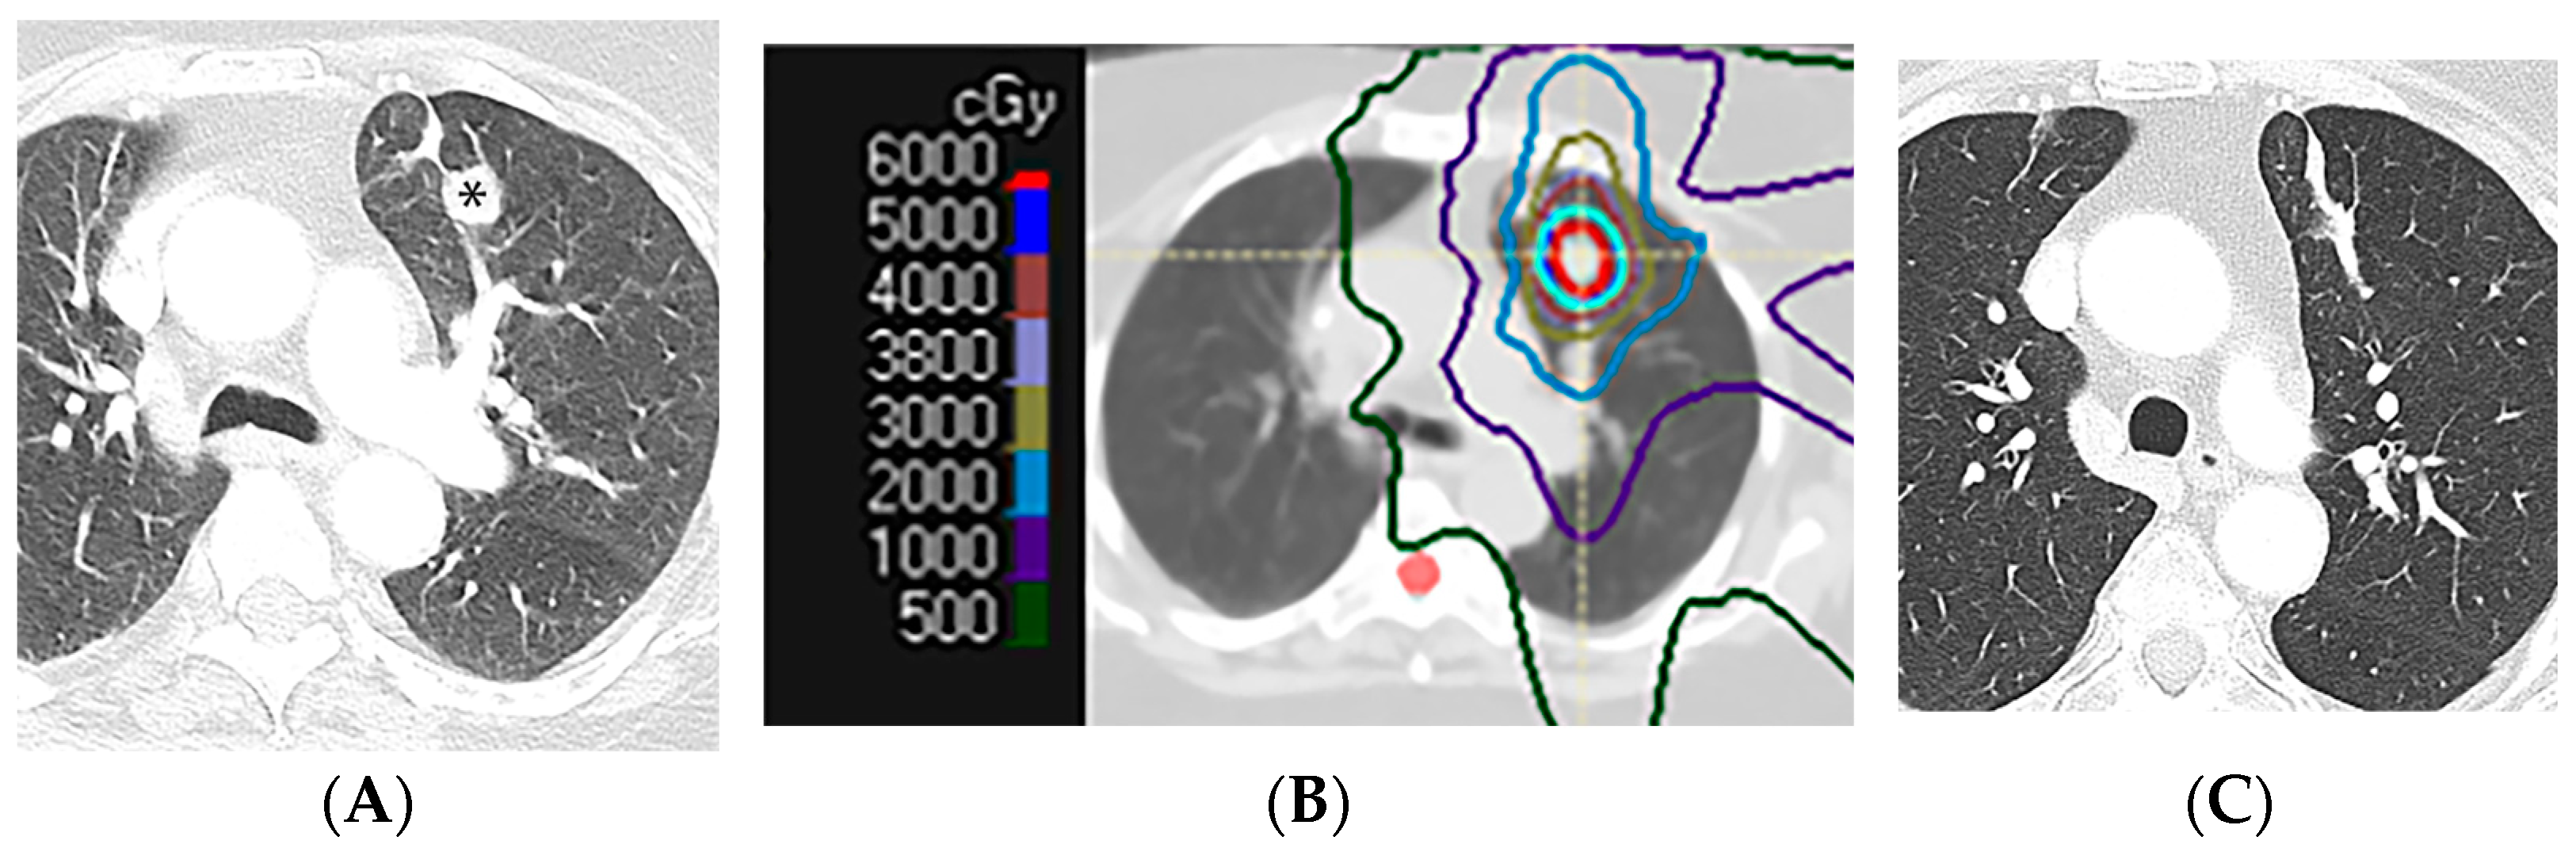

2.4. Stereotactic Body Radiotherapy